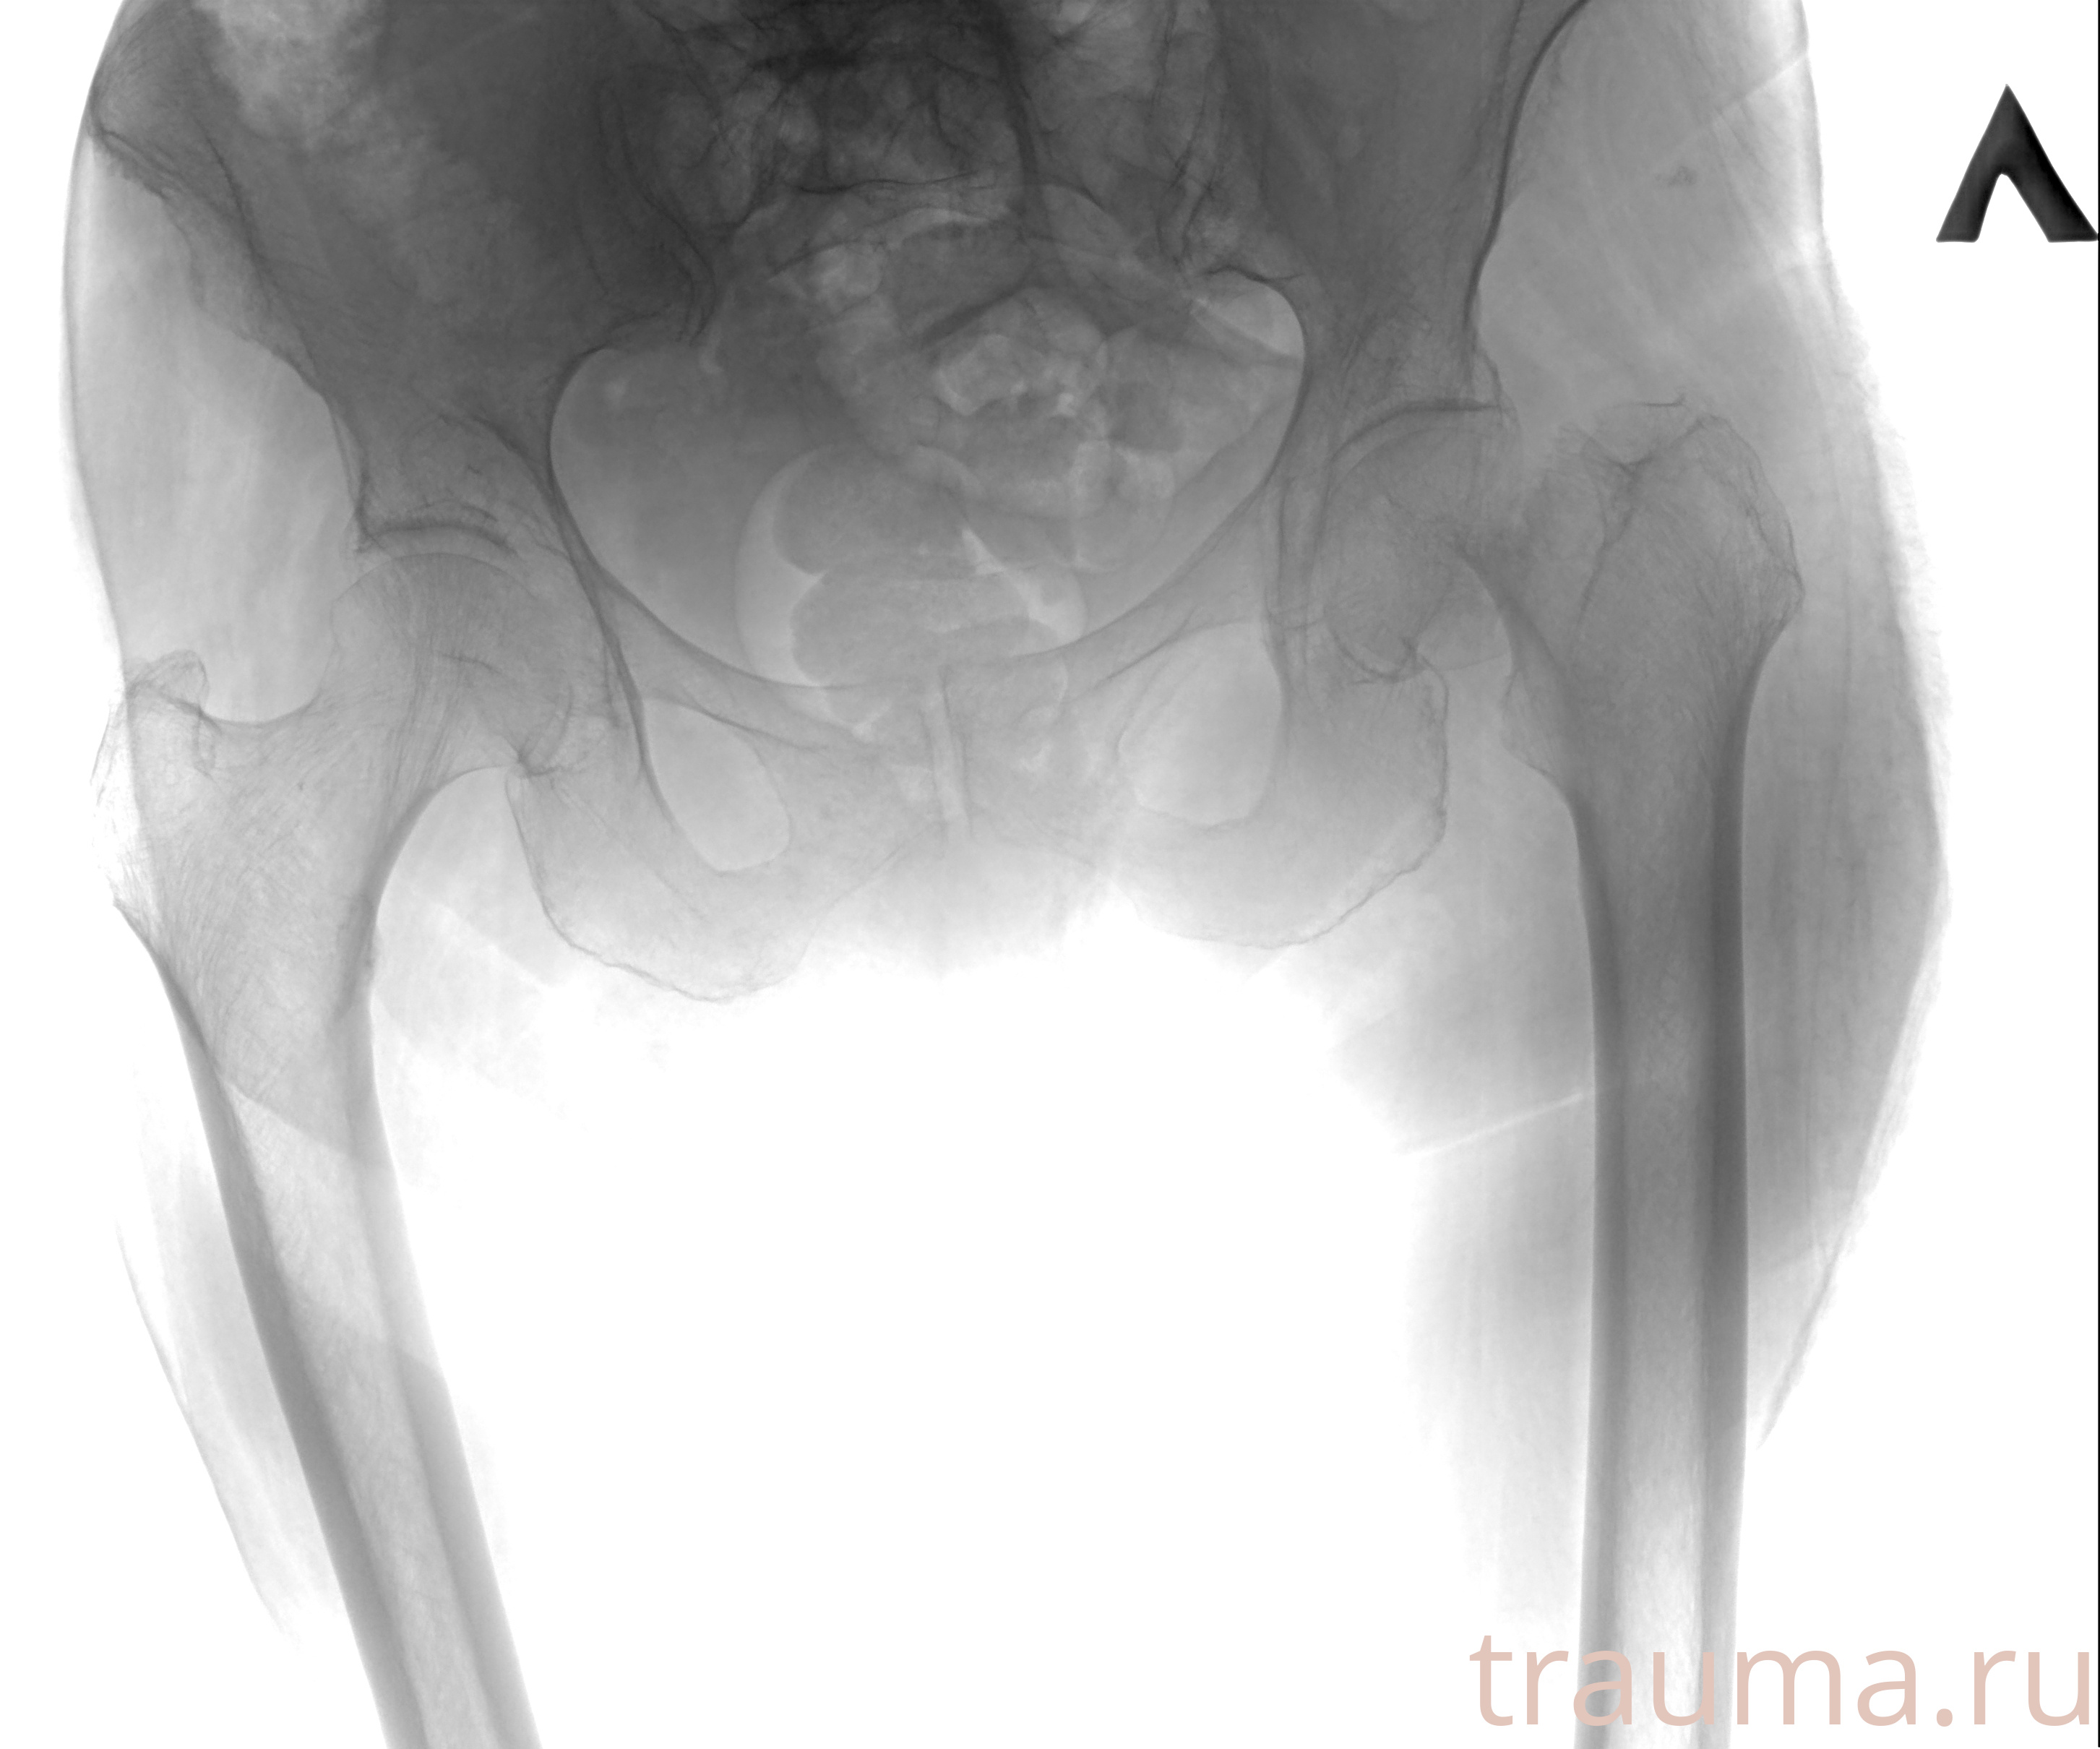

Рентген на дому: по вашему адресу приезжает врач-рентгенолог, травматолог-ортопед с мобильным рентгеновским аппаратом, проводит диагностику травмы или заболевания, делает необходимые рентгенограммы, дает рекомендации по дальнейшему лечению. Получить качественные снимки в домашних условиях возможно благодаря уникальной методике, разработанной МосРентген Центром для института  Склифосовского